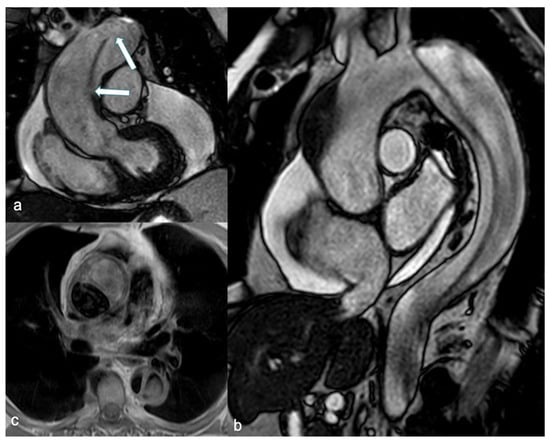

Figure 4.

SSFP breath-hold images in coronal (a) and sagittal (b) views demonstrate an intimal-medial flap involving the entire thoracic aorta, including the ascending aorta, consistent with a Stanford Type A dissection. Multiple intimal tears are visible within the flap (arrow in (a)), and massive circumferential pericardial fluid is associated. An axial SE-BB image (c) shows a hypointense true lumen and increased signal intensity in the false lumen due to slow flow. SSFP: steady-state free precession and SE-BB: spin echo-black blood.

Unenhanced SSFP sequences provide accurate and reproducible aortic measurements as well as clear visualization of the intimal-medial flap (Figure 4) [75]. Additionally, cine SSFP MRI can delineate the entry and exit zones of the intimal-medial flap and detect aortic regurgitation by identifying flow turbulence. Pereles et al. demonstrated that a short imaging protocol combining single-shot true fast imaging with steady-state precession (FISP) and cine true FISP sequences is promising for the initial, rapid, and accurate diagnosis of aortic dissection and aneurysm in less than four minutes [76]. Finally, phase contrast sequences can provide quantitative data on flow velocity and volume in both the true and false lumen.